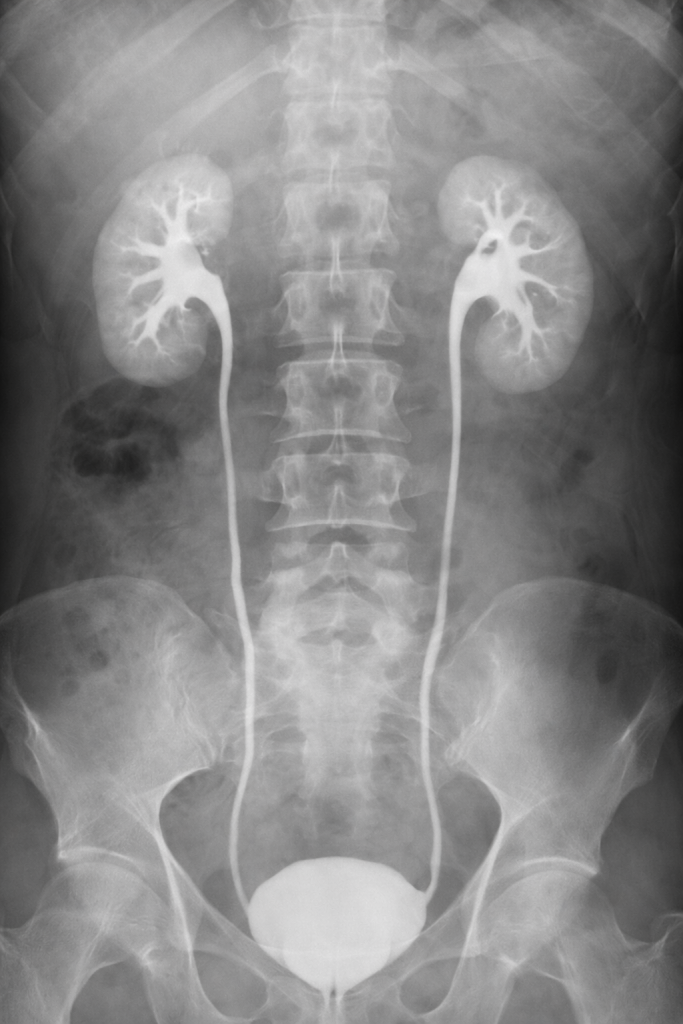

Урографія – це рентгенологічне дослідження з контрастом, яке дозволяє оцінити анатомію та функцію нирок і сечових шляхів у динаміці. На відміну від звичайного УЗД, урографія показує не лише форму органів, а й те, як вони працюють: як нирки виділяють контрастну речовину і як вона проходить по сечовивідних шляхах.

Під час дослідження пацієнту вводиться контрастна речовина, яка виводиться нирками. Далі виконуються рентгенівські знімки через певні проміжки часу, що дозволяє простежити шлях контрасту:

через нирки,

по сечоводах,

до сечового міхура.

Такий підхід дає змогу оцінити не лише будову органів, а й швидкість та повноту їх функціонування.